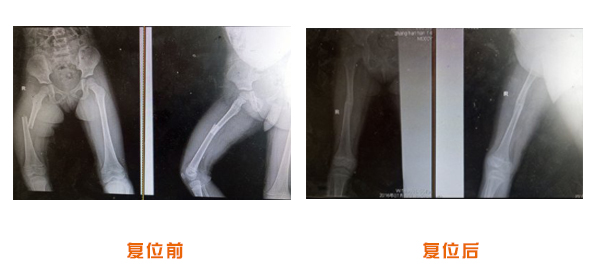

肥城市安駕莊梁氏骨科醫院是一所以梁氏手法正骨配合膏藥為特色的現代化專科醫院。

梁氏骨科術始創于清雍正年間,歷經八代,至今已有三百年歷史。據1929年泰安縣志載“梁瑞圖先生,字增生,號蓮峰,安駕莊人,精岐黃并發(fā)明接骨,凡跌打車凡跌打車軋皮不破而碎骨者......【詳細】 |